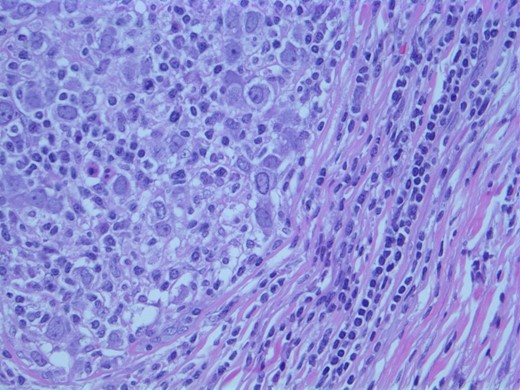

A computed tomographic (CT) scan of her chest with contrast revealed moderate right axillary lymphadenopathy and a lesion in the upper outer quadrant of the right breast measuring 1.3 × 1.2 cm (Fig. 1). A positron emission tomography (PET) scan showed a small intense focus on the right lateral breast consistent with carcinoma, significant right axillary lymphadenopathy and intense fluorodeoxyglucose hypermetabolic activity consistent with metastatic spread. Additionally, enlarged lymph nodes extending along the upper chest wall just inferior to the subclavian vessels and posterior to the pectoralis muscles were seen. A needle biopsy of the mass revealed an extensive involvement of poorly differentiated infiltrating carcinoma (Fig. 2). The tumor showed large nuclei with eosinophilic cytoplasm and prominent nucleoli consistent with apocrine differentiation (Fig. 3). There was a significant inflammatory response to the infiltrating tumor noted. No lymphovascular invasion was identified within the core biopsies. The specimen was estrogen and PR negative as well as HER-2/neu negative.

Photomicrograph: large nuclei with eosinophilic cytoplasm and prominent nucleoli consistent with apocrine differentiation.